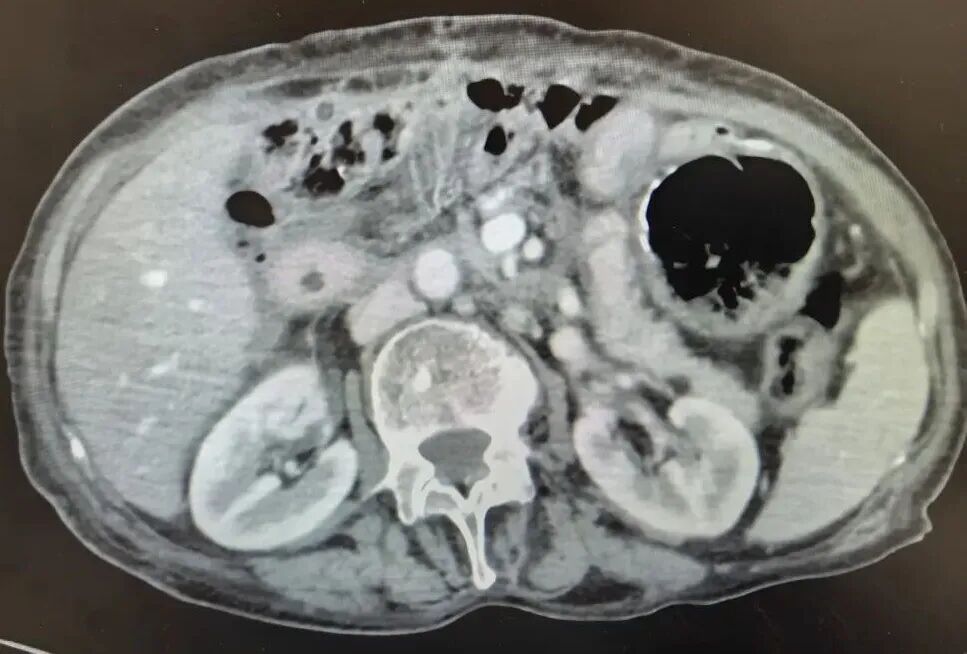

仅仅过了四天,李奶奶的病情进一步恶化,出现腹部胀痛等症状,精神状态也日渐萎靡。李奶奶家人带着她来到我院普外科就诊。经过全面的检查,李奶奶被确诊为「胆总管囊状扩张症(I 性)并胰头段癌变,胆总管结石、梗阻性黄疸」。肿瘤已经导致胆总管部分阻塞,

胆汁排出受阻,引发严重黄疸和感染。

付博士指出:患者虽然年龄大,但是三博手术室的数字化可视平台建设(如术者在实际手术操作时,随时可在同一视野内实时与 CT 核磁等影像同步对比)、麻醉和重症团队的良好配合、手术团队高难度复杂手术的经验积累等待,都有力保障团队有充足的信心在计划范围内完成手术操作,加上外科医护围手术期精细化管理的实力等,均是得以圆满完成本次挑战的坚实基础。